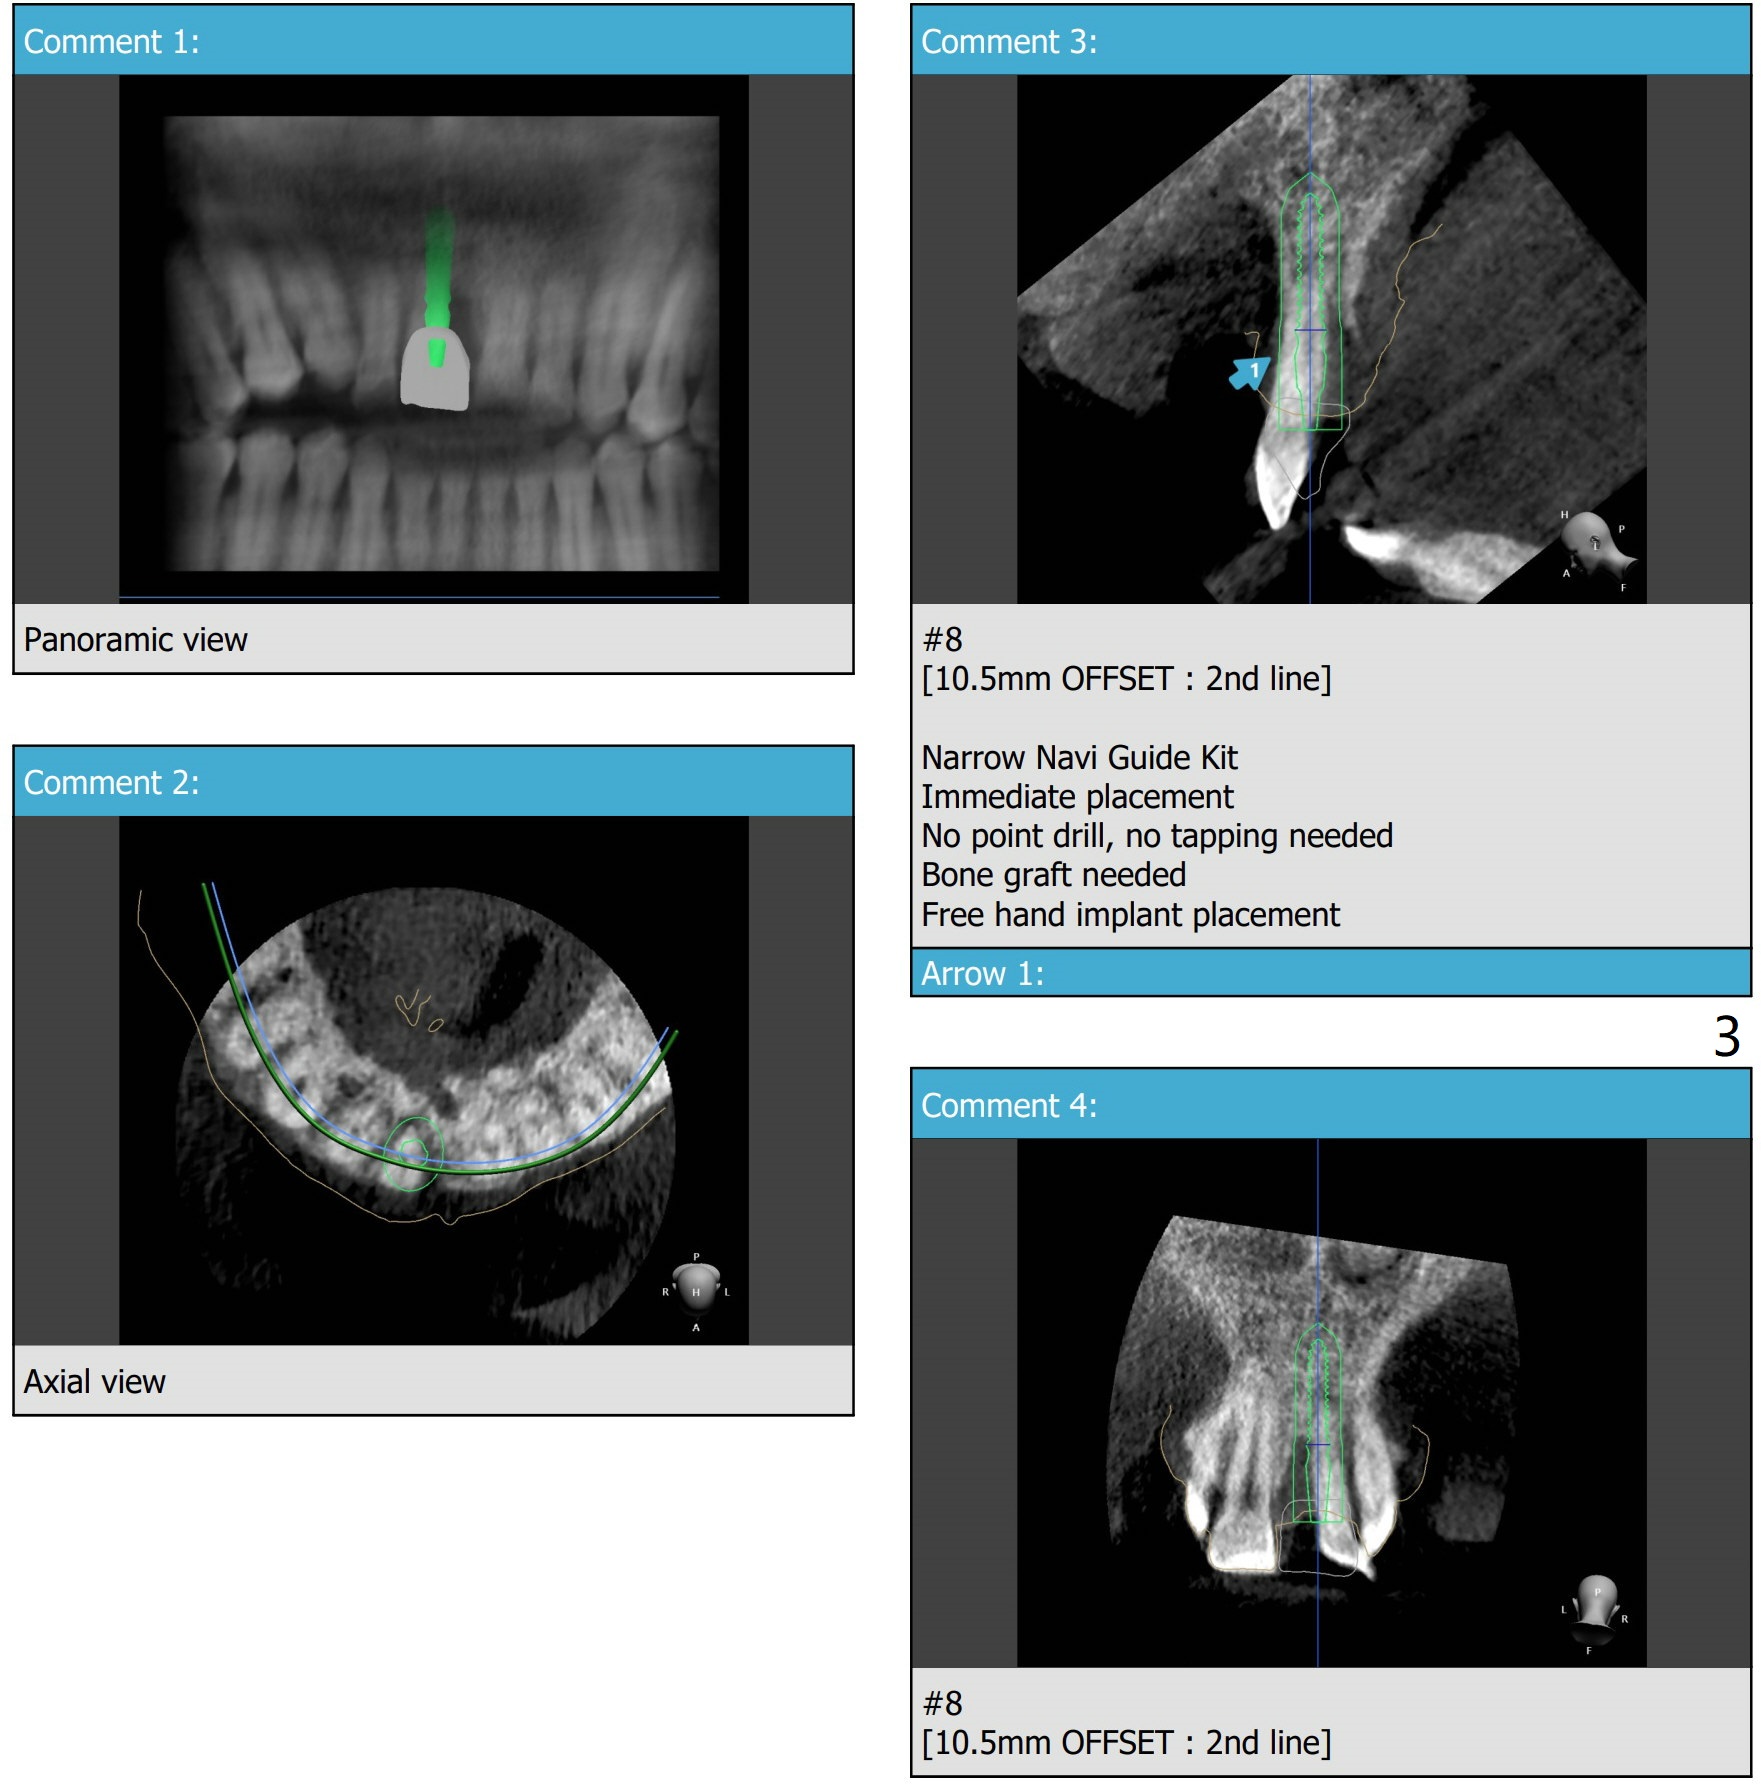

Mesial Placement

Return to Protect Graft